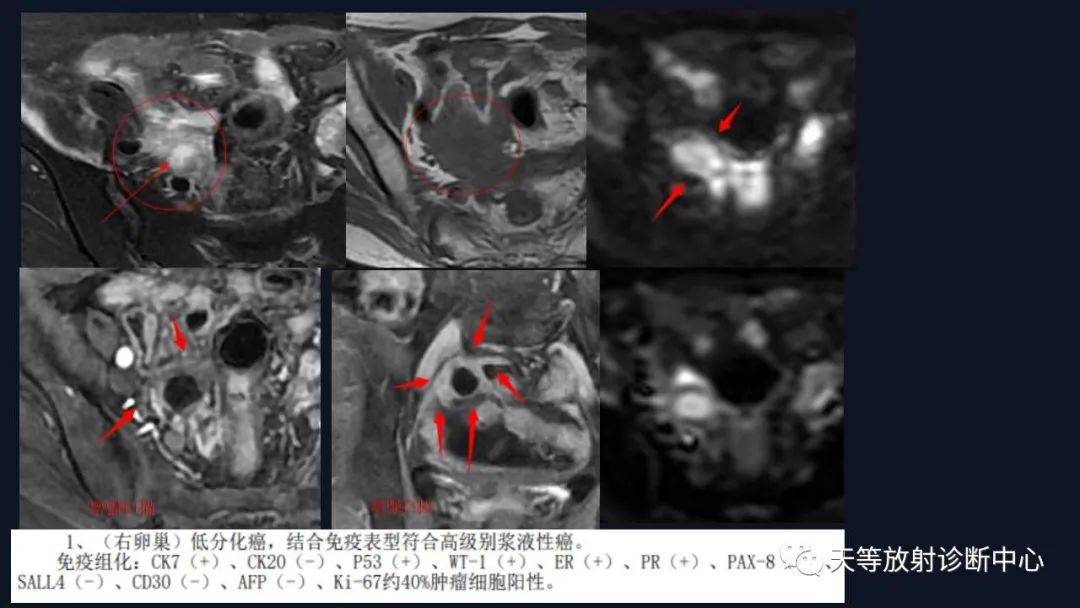

1、浆液性囊腺瘤 :浆液性囊性肿瘤较常见,浆液性肿瘤好发的平均年龄为40岁以上,表现为纯囊性,可呈多囊改变,T1WI呈低信号、T2WI呈高信号、DWI呈低信号,增强后无实性成分强化。

3、浆液性表面乳头状肿瘤是卵巢浆液性肿瘤的一种不同的亚型,此类型肿瘤局限于卵巢表面,保留卵巢的正常大小和形状,表现为囊实性软组织肿块,具有表面乳头状突起特征性影像特征。

交界性肿块呈囊实性、多房改变, T1WI呈高信号、T2WI呈高信号、病灶实性部分DWI以较高信号为主,增强后实性成分均呈结节状强化。